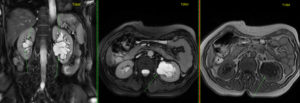

- МРТ соединяет свойства электромагнитного поля. Оно передает информацию в виде высокочастотных импульсов, которые компьютер считывает в виде четких срезов толщиной не более 1–2 мм. Последние модели сканеров формируют трехмерное изображение почки с прилегающими кровеносными сосудами, что необходимо при сложных операциях, трансплантации.

Что видно на снимках МРТ

При почечной недостаточности МРТ почек лучше показывает причину дисфункции органа. На срезах хорошо просматриваются:

- патологические очаги в лоханке и надпочечниках;

- некроз ткани при гибели канальцев;

- негативные изменения в структуре органа;

- размер новообразования;

- недостаточность кровообращения и выделения мочи.

- Опытный диагност по снимкам определяет виды и характер образований, обнаруживает метастазы, устанавливает стадию онкологии.

Что видно на МРТ-снимках

- наличие/отсутствие патологии органа;

- размер почек, состояние сосудов (наличие застойных процессов);

- наличие опухоли;

- наличие изменений в структуре тканей;

- степень функционирования органа, наличие патологии сосудов, почечной недостаточности, патологических процессов.